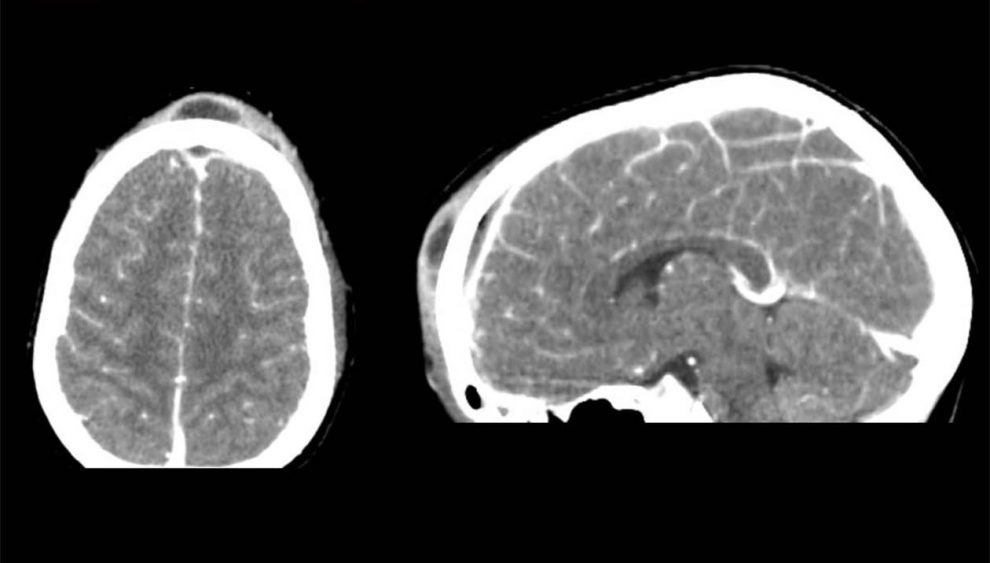

«Ένα πολύ σοβαρό περιστατικό αντιμετωπίζεται αυτές τις μέρες με επιτυχία στο νοσοκομείο μας. Παιδί 8 ετών, με βαριά επιπλεγμένη ρινοκολπίτιδα, μεταφέρθηκε εσπευσμένα στο Πανεπιστημιακό Νοσοκομείο Ηρακλείου. Ο κλινικός και απεικονιστικός έλεγχος ανέδειξαν βαριά μετωπιαία κολπίτιδα και οστεομυελίτιδα, ηθμοειδίτιδα, καθώς και συνοδό ενδοκρανιακό απόστημα. Η ζωή του παιδιού κινδύνευε σοβαρά και αποφασίστηκε χειρουργική αντιμετώπιση. Στο χειρουργείο, υπό γενική αναισθησία, παροχετεύσαμε επιτυχώς το πύο από το μετωπιαίο κόλπο και τις ηθμοειδείς, με ενδοσκοπική προσπέλαση. Ακολούθως, οι νευροχειρουργοί διενέργησαν ανοικτή κρανιοτομή και παροχέτευσαν το υποσκληρίδιο απόστημα του εγκεφάλου. Η ανταπόκριση του μικρού ασθενούς ήταν εντυπωσιακή. Μετά από σύντομη παραμονή στη ΜΕΘ Παίδων, βρίσκεται πλέον, σαφώς βελτιωμένος, στην παιδιατρική κλινική. Η συνεργασία όλων των εμπλεκόμενων ειδικοτήτων, ΩΡΛ, νευροχειρουργών, αναισθησιολόγων, παιδιάτρων και εντατικολόγων, ήταν εξαιρετική. Και η συμβολή όλων καθοριστική ώστε να διαφύγει τον κίνδυνο ο μικρός ασθενής μας».